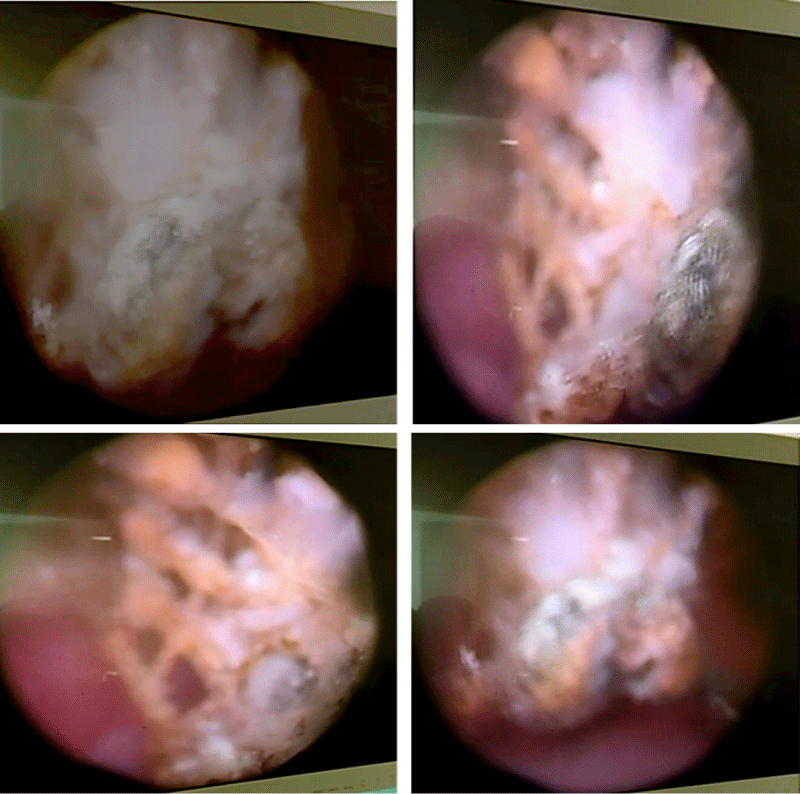

Figure 1:

Cystoscopic view showing a bladder stone formed on exposed intravesical mesh fibers.